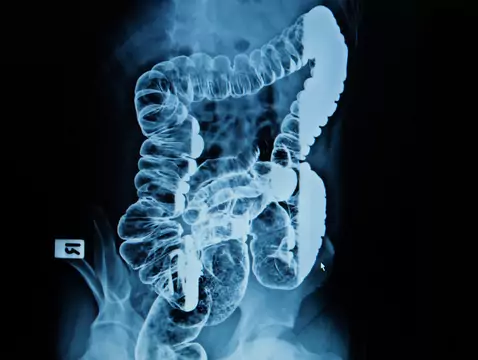

La colposcopia es una de las pruebas complementarias al diagnóstico de las lesiones cancerosas del cuello uterino, la vagina y la vulva. Se realiza con mayor frecuencia en caso de un resultado citológico anormal, que es el primer paso en el diagnóstico del cáncer de cuello uterino. Las numerosas posibilidades que ofrece este examen hacen que sea cada vez más popular.

El resultado de un examen citológico no siempre es suficiente para realizar un diagnóstico correcto y requiere una verificación colposcópica e histopatológica. La combinación de citología y colposcopia proporciona aproximadamente un 95% de precisión en el diagnóstico de las anomalías cervicales, y los mejores resultados diagnósticos en el diagnóstico de las lesiones epiteliales precoces se obtienen complementando la citología con un examen virológico completo, en particular para los virus altamente ionógenos.

La colposcopia es sólo un examen complementario de las pruebas citológicas y no permite establecer un diagnóstico definitivo; sólo puede sugerir una patología. Para un diagnóstico completo, es necesaria la verificación histopatológica de la muestra tomada durante la biopsia dirigida para diferenciar entre carcinoma invasivo y lesiones displásicas.